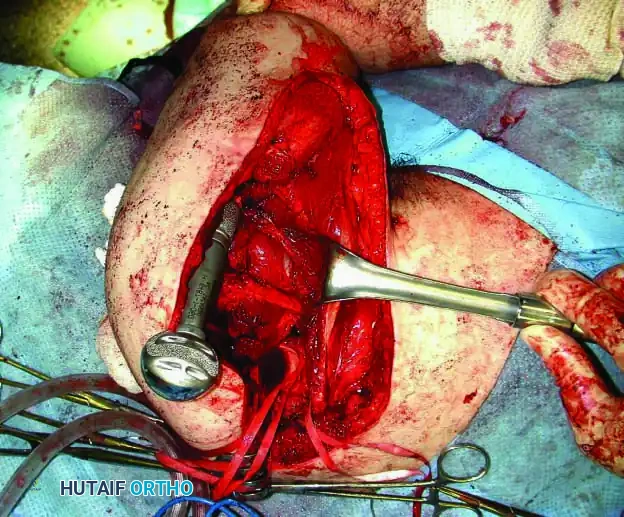

Intraoperative Imaging and Margin Assessment

Continuous intraoperative assessment using fluoroscopy and frozen section pathology is mandatory. The following images demonstrate various stages of complex upper extremity resections, allograft preparations, and prosthetic implantations across the humerus and elbow joint.